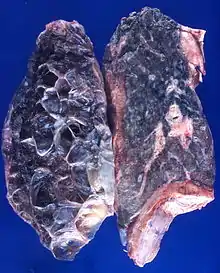

Left lung completely affected by bullae shown in contrast to a normal lung on the right. | |

In the lungs, emphysema involves enlargement of the distal airspaces,[2] and is a major feature of chronic obstructive pulmonary disease (COPD). Other pneumatoses in the lungs are focal (localized) blebs and bullae, pulmonary cysts and cavities.